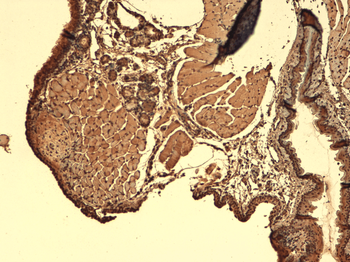

应用稀释比例:WB (1:1000), IHC (1:1000)

应用注释:1 µg/ml of SMC-391 was sufficient for detection of hNIS in 20 µg of transfected COS-7 cell membrane lysate by ECL immunoblot analysis using Goat anti-mouse IgG:HRP as the secondary antibody.